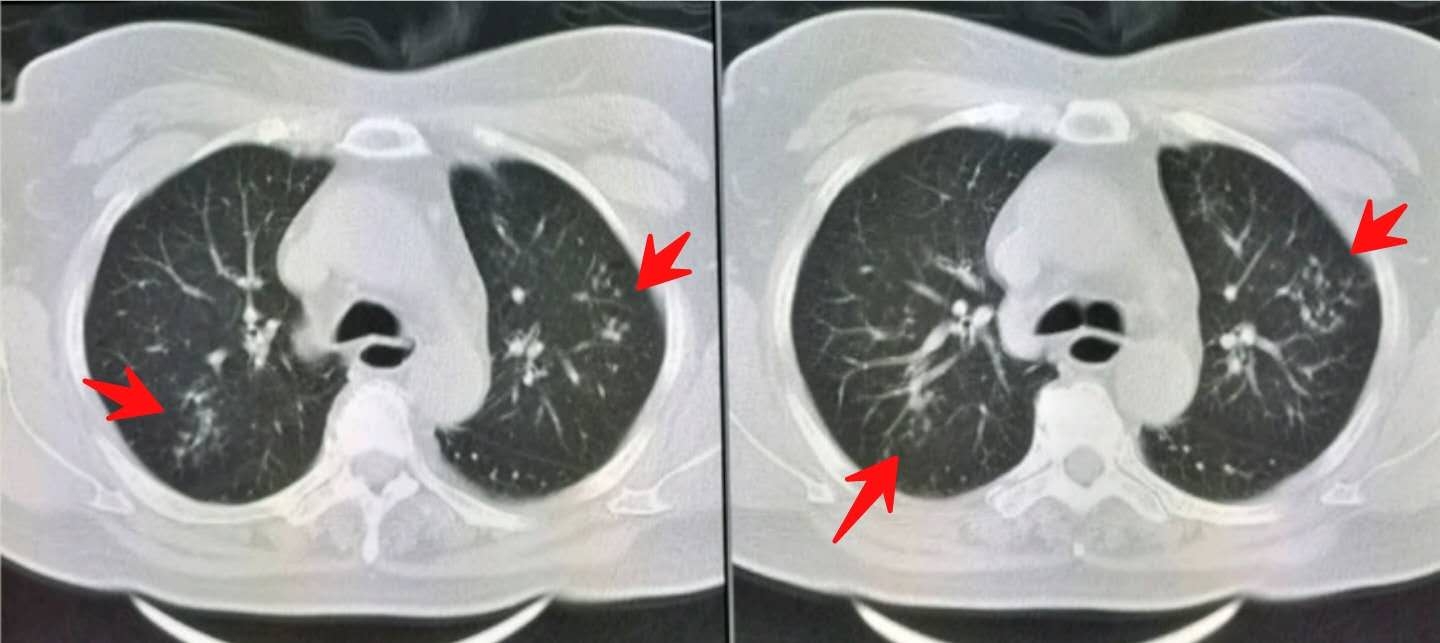

挂了呼吸科专家号,医生说做个肺部CT吧,这个年纪应当查一下:

胸部CT发现双肺多发小斑点状影,提示沿支气管扩散的肺内炎症。

同时我们注意到她的食管下段扩张(绿色圈):